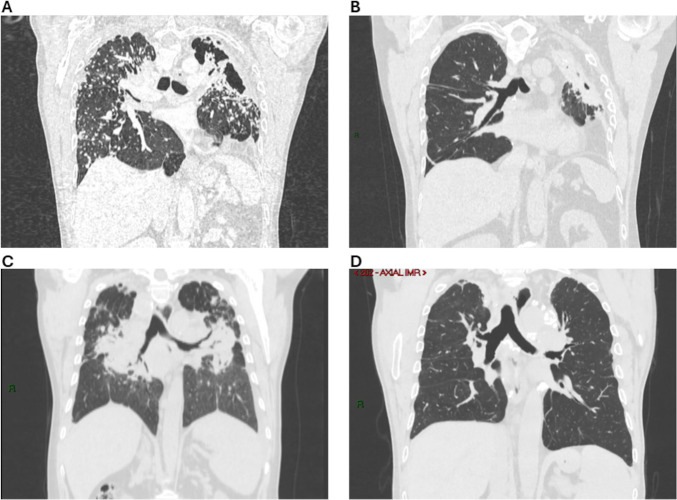

背景:矽肺病是由吸入结晶二氧化硅引起的,是一个日益严重的全球健康问题,由于人造石的使用增加而加剧。对于终末期矽肺,肺移植可能是唯一可行的治疗方法。虽然双肺移植比单肺移植具有长期生存效益,但在矽肺患者中没有评估这一问题。研究问题:我们的研究旨在评估矽肺患者接受肺移植的生存结果,比较单肺移植和双肺移植。研究设计和方法:这是一项单中心回顾性队列研究,纳入了2006年3月至2024年3月期间在我中心接受肺移植治疗矽肺的所有患者。结果:本中心研究期间共进行肺移植778例,其中矽肺移植40例(5.14%),单肺移植25例,双肺移植15例。双肺移植受者由于粘连和移植困难,手术过程更具挑战性,血制品体积显著增加(8.00±15.13单位vs 24.85±24.41单位,p=0.023),缺血时间显著延长(243.63±85.36分钟vs 327.67±95.23分钟,p=0.009)。单肺组与双肺组的死亡或再移植风险无显著差异(HR 1.163, 95% CI 0.473 ~ 2.861; p=0.74)。此外,两组移植后1年和3年肺功能测试结果无显著差异(36个月随访预测前2%用力呼气量51.93±22.43 vs 66.67±32.09,p=0.25)。结论:考虑到矽肺患者肺移植需要复杂的外科手术,更长的缺血时间,对血液制品的需求增加以及缺乏明确的证据支持双肺移植,考虑对这些患者优先进行单肺移植可能是谨慎的。

Results: During the study period, our centre conducted 778 lung transplantations, 40 of them (5.14%) were for silicosis, 25 single lung transplants and 15 double lung transplants. Double lung transplantation recipients experienced a more challenging surgical course due to adhesions and difficulty in explantation, associated with a significantly higher volume of blood products (8.00±15.13 units vs 24.85±24.41 units, p=0.023) and longer ischaemic times (243.63±85.36 min vs 327.67±95.23 min, p=0.009). There was no significant difference in the risk of death or re-transplantation in the single lung versus the double lung group (HR 1.163, 95% CI 0.473 to 2.861; p=0.74). Additionally, the two groups had no significant disparities in pulmonary function test results at 1 and 3 years post-transplant (51.93±22.43 vs 66.67±32.09 forced expiratory volume in the first second percent predicted at 36 months follow-up, p=0.25).